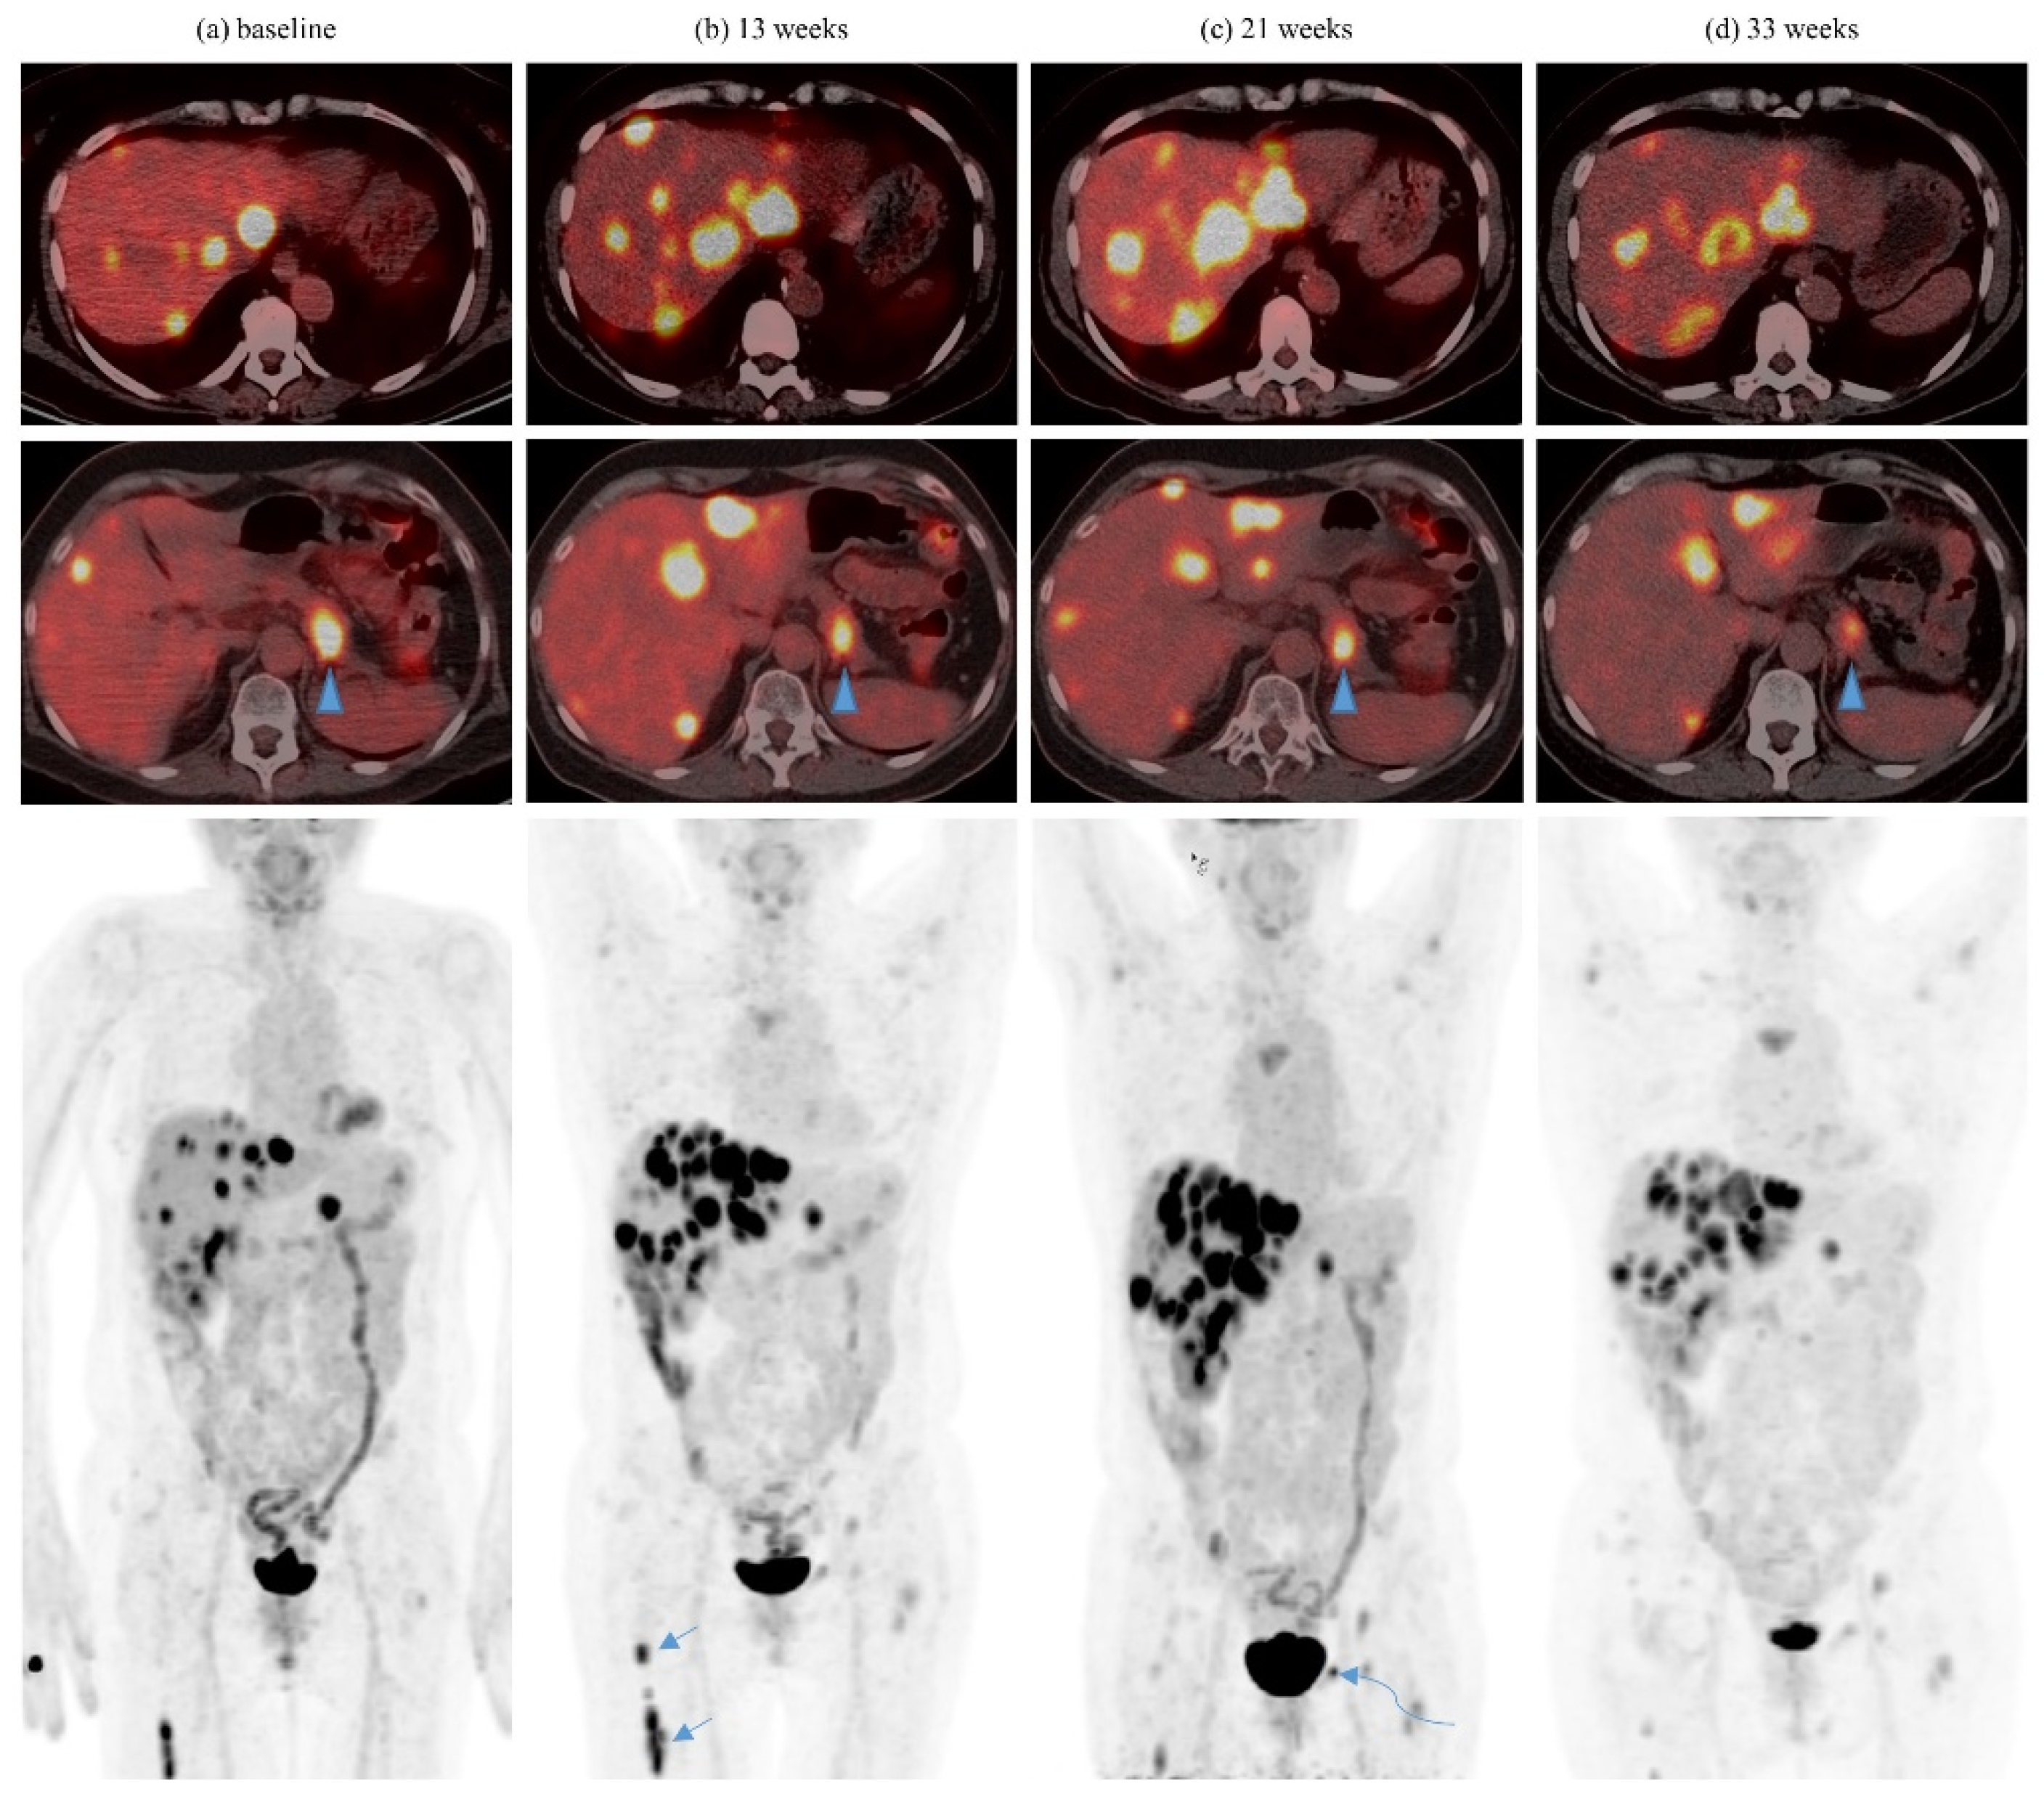

| Dissociated response | 9 | 60 | 13 | 41.9 | 22 | 47.8 |

| Abscopal response | 4 | 26.7 | 5 | 16.1 | 9 | 19.6 |

| 5 | Pembrolizumab | 3 6 | 8Gy/1 27Gy/3 | Yes Yes | Femur Pubic bone | Liver, several | 1 | Concurrent axitinib from prior line of treatment maintained |